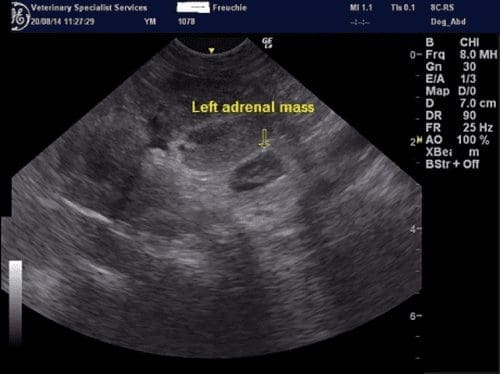

A left sided adrenal mass was identified with no obvious signs of invasion into the major vessels. The maximum width was 0.9cm and the adrenal had lost its peanut shape. The right adrenal was unremarkable.